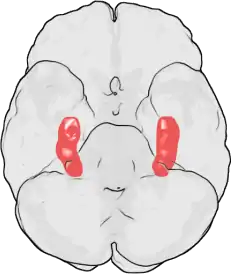

There are several areas of the brain associated with the highly specialized form of memory for faces.

Fusiform face area

The fusiform face area (FFA) is associated with facial recognition. It is generally located on the fusiform gyrus in the temporal lobe, but its precise location varies between individuals.[3] The FFA has been found to show a degree of lateralization, or what side of the brain the activity is likely to be found.[3] Typically, it is larger in the right hemisphere of the brain.[3] It is widely accepted that the FFA is involved in the encoding and retrieval of memory for faces and other familiar categorical processing.[4]

Damage to the FFA has been shown to lead to severe deficits in facial recognition and processing.[5] These deficits can lead to difficulty in maintaining normal social relationships over an extended period.

Friends and foes are represented differently in the brain. The fusiform cortex, posterior cingulate gyrus, amygdala, and areas involved in motivational control were differentially activated as a function of previous social encounters. In general, these areas were more active when faces were perceived as foes rather than friends.[43]